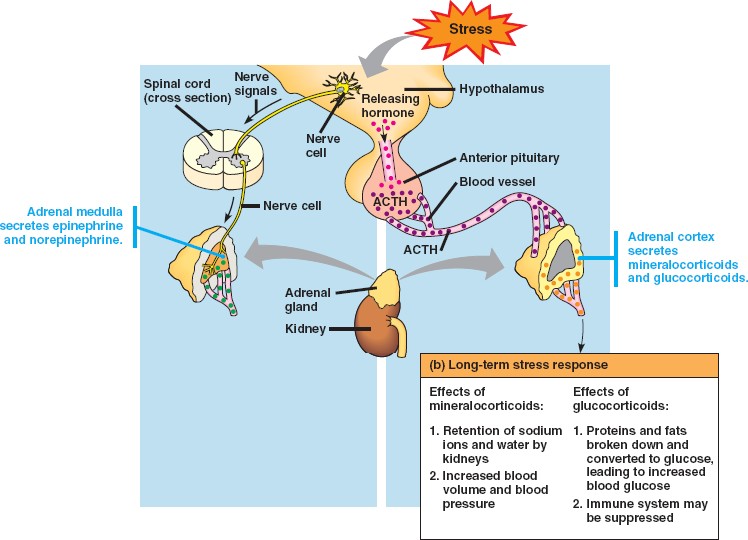

45_13StressAdrenals

45_13StressLong

adrenal_cortex.html

epinephrine.html